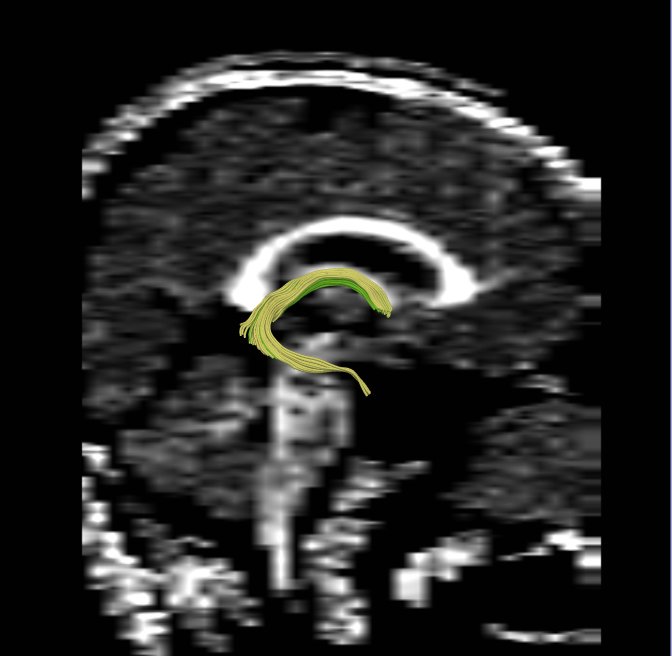

We apply fiber tractography to quantify fornix Fractional Anisotropy (FA) in schizophrenia. Two ROI method (shown in the figures) were used to extract left and right fornix in 34 chronic schizophrenia subjects and 40 matched controls, and mean FA along the entire tract was extracted separately for the left and the right sides and compared between groups. Preliminary data indicate bilateral decreased FA in the fornix of schizophrenics. | We apply fiber tractography to quantify fornix Fractional Anisotropy (FA) in schizophrenia. Two ROI method (shown in the figures) were used to extract left and right fornix in 34 chronic schizophrenia subjects and 40 matched controls, and mean FA along the entire tract was extracted separately for the left and the right sides and compared between groups. Preliminary data indicate bilateral decreased FA in the fornix of schizophrenics. | ||

Fiber tracts, especially those interconnecting the frontal and temporal lobes, are likely implicated in schizophrenia. Very few studies have focused on the fornix. The goal of this project is to examine the integrity of fibers in the fornix in patients with schizophrenia.